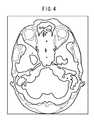

FIG. 4 is a diagram showing an example of a specified standard tomographic image according to the first embodiment;

Then, in step S4, the standardtomographic image identifier20 identifies, from the three-dimensional standard image acquired in step S2, a standard tomographic image corresponding to the medical tomographic image selected in step S3. At this time, the standardtomographic image identifier20 identifies a standard tomographic image, which is in conformity with the medical tomographic image at a level higher than a predetermined value, and which is in closest conformity with the medical tomographic image, according to the above-described positioning process. The location (position) of the section in the three-dimensional standard image is recognized, which corresponds to the section that has been selected by the user in the three-dimensional medical image.FIG. 4 shows an example of the identified standard tomographic image.

If the section selected by the user is an axial section, then the standardtomographic image identifier20 may determine the distance by which the selected medical tomographic image is spaced from the top of the head of the examinee, and may further identify the image of a section that is spaced by the distance from the top of the head of the model subject as a standard tomographic image. Since the examinee, the three-dimensional medical image of whom has been captured, and the model subject, the three-dimensional standard image of which is recorded in theimage database12, are of the same gender, age, height, etc., the medical tomographic image and the standard tomographic image define tomographic images, which are at substantially the same position.